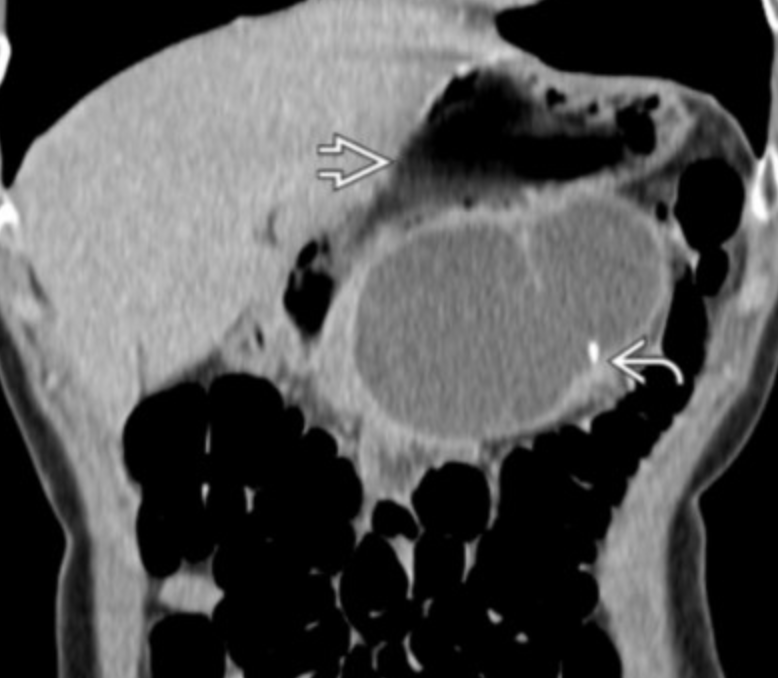

Solid and Pseudopapillary Neoplasma (SPEN)

• Well defined

• Typically in tail of pancreas

• Hypoechoic on US

• Solid mass with hemorrhagic and necrotic focus

• Low risk but still some risk of malignancy

• Women, <35